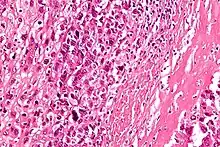

Intermediate-magnification micrograph of an osteosarcoma (center and right of image) adjacent to non-malignant bone (left-bottom of image): The top-right of the image has poorly differentiated tumor. Osteoid with a high density of malignant cells is seen between the non-malignant bone and poorly differentiated tumor (H&E stain).

High-magnification micrograph showing osteoid formation in an osteosarcoma H&E stain

Microscopically: The characteristic feature of osteosarcoma is presence of osteoid (bone formation) within the tumor. Tumor cells are very pleomorphic (anaplastic), some are giant, numerous atypical mitoses. These cells produce osteoid describing irregular trabeculae (amorphous, eosinophilic/pink) with or without central calcification (hematoxylinophilic/blue, granular)—tumor bone. Tumor cells are included in the osteoid matrix. Depending on the features of the tumor cells present (whether they resemble bone cells, cartilage cells, or fibroblast cells), the tumor can be subclassified. Osteosarcomas may exhibit multinucleated osteoclast-like giant cells.[22]